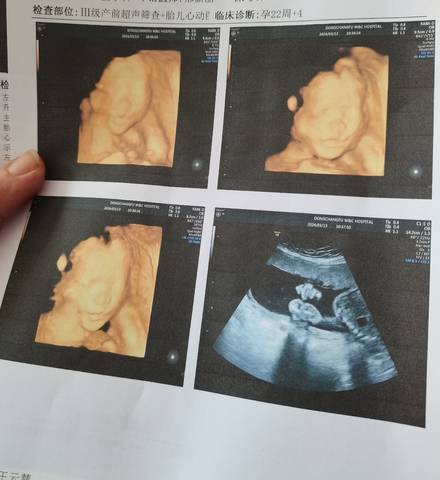

顺利通过了四维 第一次宝宝趴着 第二次一次过了😁 模拟了一下体重有520克了😁 不知道男女 不过看四维成像有点像女宝🤰